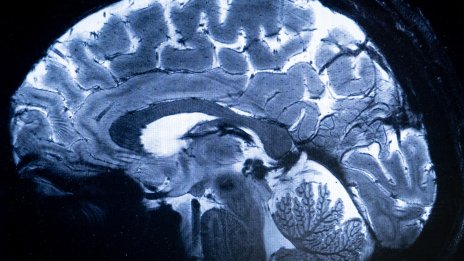

Мозъчните чипове са тук и не са толкова страшни, колкото звучат

Последните две години бележат скок към по-сложни устройства, които обещават да лекуват по-широк кръг от състояния с по-прости процедури